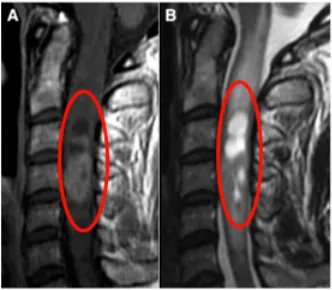

35岁女性患者礼小姐因长期伏案工作出现肩颈部间歇性疼痛症状,初期未予重视,仅在疼痛加剧时接受按摩理疗缓解。随病情进展,患者出现夜间疼痛影响睡眠,伴有上肢麻木无力症状持续一月余,遂行医学检查。MRI检查显示异常信号,进一步确诊为脊髓髓内室管膜瘤,伴随脑干延髓广泛水肿表现。

患者赴德接受Krauss教授主刀的手术治疗。手术采用后方入路,在体感诱发电位监测下实施肿瘤切除,确保无神经损伤的前提下实现肿瘤全切。术后12天复查证实肿瘤完全切除,术后水肿基本消失,颈椎疼痛症状明显缓解。